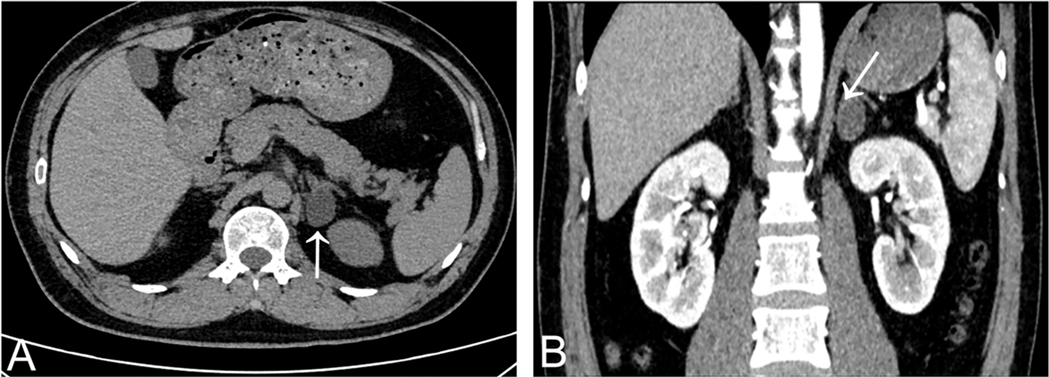

A 37-year-old man diagnosed with hypertension for 3 years was referred to the cardiology department for evaluation of possible secondary hypertension. He denied prior cerebrovascular accidents or cardiovascular diseases. Anthropometric measurements revealed a height of 175 cm and weight of 74 kg, yielding a body mass index (BMI) of 24.16 kg/m2. His peak recorded blood pressure (BP) was 185/130 mmHg. Despite daily therapy with nifedipine extended-release tablets 30 mg and sacubitril/valsartan 200 mg, BP control remained suboptimal: office BP was 160/110 mmHg, while 24 h ambulatory BP monitoring showed an average of 134/85 mmHg (daytime: 140/93 mmHg; nighttime: 124/73 mmHg). Laboratory findings were as follows (Table 1): hemoglobin 156 g/L, white blood cell count 10.07 × 109/L, platelet count 243 × 109/L; serum potassium 3.26 mmol/L, sodium 142.7 mmol/L, calcium 2.36 mmol/L; alanine aminotransferase (ALT) 60 U/L, aspartate aminotransferase (AST) 28 U/L; uric acid 455 μmol/L, triglycerides 1.96 mmol/L, total cholesterol 5.31 mmol/L, low-density lipoprotein cholesterol 3.73 mmol/L, and fasting blood glucose 4.95 mmol/L; creatinine 104.1 μmol/L, estimated glomerular filtration rate (eGFR) 80.22 ml/min/1.73 m2. Routine urinalysis revealed no abnormalities (negative for protein, glucose, ketones, and leukocytes). To avoid interference with aldosterone-to-renin ratio (ARR) assays, antihypertensive therapy was switched to doxazosin 8 mg daily and verapamil 240 mg daily over a one-month period. Direct renin concentration and aldosterone levels were measured using a chemiluminescent immunoassay platform at our center. Hormonal evaluation in the upright position revealed: plasma aldosterone concentration (PAC) 937.18 pmol/L, suppressed renin 1.60 pg/ml, and ARR 585.74. In the supine position, results showed: PAC > 1,000 pmol/L, suppressed renin 1.71 pg/ml, and incalculable ARR due to unmeasurably high aldosterone levels. Circadian rhythm of serum cortisol and adrenocorticotropic hormone, plasma free metanephrines, and thyroid function were within normal range. The combination of markedly elevated aldosterone and suppressed renin suggested probable primary aldosteronism (PA). A supine saline suppression test was subsequently performed, involving intravenous infusion of 2 L of 0.9% sodium chloride solution over 4 h, with blood samples collected at baseline and post-infusion. Results demonstrated: baseline PAC > 1,000 pmol/L, renin 1.28 pg/ml; Post-infusion PAC > 1,000 pmol/L, renin 1.04 pg/ml. These findings confirmed autonomous aldosterone excess, supporting a PA diagnosis. Contrast-enhanced adrenal computed tomography (CT) scan identified a 1 cm left adrenal nodule with an attenuation value of 1 Hounsfield unit (HU), consistent with a lipid-rich adenoma (Figure 2).

Figure 2. Adrenal gland CT scan showed a lipid-rich left adrenal nodule (arrows) [(A) non-contrast enhanced CT; (B) contrast-enhanced CT].